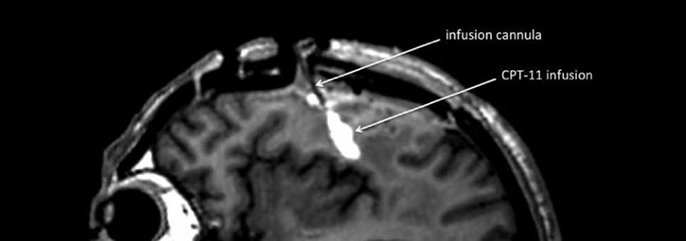

Targeted drug delivery will breach the blood-brain barrier

Biological safeguards that protect the brain from blood-borne infections or toxins are crucial to survival. But these barriers can backfire when they don’t allow therapeutic agents to reach the brain. Most chemotherapy for brain tumors is given orally or intravenously and causes significant side effects – often with little impact on the cancer itself.

“For years, neurologists have wrestled with a quandary: Do drugs for certain brain conditions fall short because they’re ineffective, or do they simply fail to cross the blood-brain barrier?” says Krystof Bankiewicz, MD, Ph.D, professor of neurosurgery.

Bankiewicz is testing a convection-enhanced drug delivery system that enables a chemo drug to be infused directly into the brain of patients with glioblastoma, a fatal brain tumor. Since the bloodstream is bypassed, higher doses can be given, hopefully with fewer side effects.

The upcoming year will mark the conclusion of Phase I of this trial and the launch of a parallel trial for children with brain tumors. In two other trials, he is testing gene-carrying viruses infused directly into the putamen, the dopamine producing part of the brain, in patients with Parkinson’s, and there are plans to develop trials for patients with Alzheimer’s and Huntington’s disease.

Bankiewicz and collaborators will be anxiously awaiting results. Could convection enhanced delivery revolutionize the treatment of the most intractable of brain diseases?